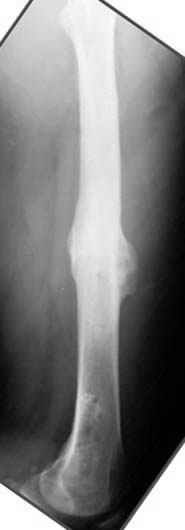

Несколько снимков из моей коллекции, чтобы разьяснить, почему мы до сих пор делаем различные варианты остеотомии.

N3 рисунок окончательный снимок, после операции моя рентгенограмма должен выглядеть примерно как эта картина. На N4 снимке клин перед удалением; N5 послеоперации 3 нед.; N6 окончательная рентгенограмма.

пластическая модель; и коррекция бедра аппаратом Илизарова.